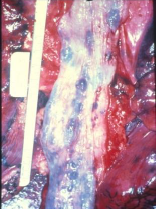

Pathology

Meckel's diverticulum failure of involution of omphalo-mesenteric duct